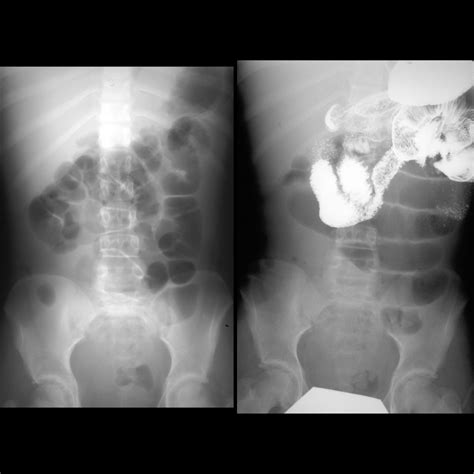

The Small Bowel Follow Through (SBFT) is a radiological examination that uses X-rays to visualize the small intestine. This procedure is particularly useful for detecting abnormalities such as strictures, obstructions, tumors, and inflammatory conditions like Crohn’s disease. The SBFT involves ingesting a barium solution, which coats the lining of the small intestine, making it visible on X-ray images.

• X-ray Imaging: As the barium solution moves through the small intestine, a series of X-ray images are taken at regular intervals. This allows the radiologist to observe the movement of the barium and identify any abnormalities.